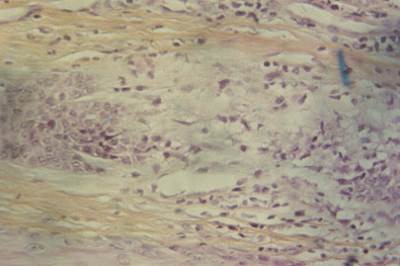

L’examen histopathologique des biopsies cutanées montre: (Photos 6,7)

• Une hyperkératose orthokératosique épidermique et folliculaire très importante.

• Un épiderme acanthosique avec quelques crêtes.

• Des annexes épidermiques proches de la normale, à l’exception sur l’ensemble des prélèvements, de l’absence totale de glandes sébacées.

• La présence, par endroit, d’un infiltrat periannexiel lymphoplasmocytaire.

• La présence sur une section d’un granulome contenant des débris de kératine à la base d’un follicule pileux.